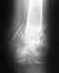

Лечебная иммобилизация осуществлена КДА Г.А. Илизарова, как видно на рентгенограмме (фиг.5). Базовое кольцо КДА Г.А. Илизарова наложено в нижней трети предплечья с фиксацией на 2-х взаимоперекрещивающихся спицах Киршнера, проведенных через обе кости. 1-е полукольцо КДА Г.А. Илизарова наложено на границе средней и верхней трети предплечья, фиксированное на одной спице, проведенной через обе кости предплечья, и 2-е полукольцо КДА Г.А. Илизарова - на уровне диафизов пястных костей с разгрузкой лучезапястного сустава после проведения основного этапа операции.

Сращения отломков ладьевидной кости наступило через 2 месяца от момента операции, как видно на контрольной рентгенограмме (фиг.6). Функция конечности восстановлена полностью. Военно-врачебной комиссией признан годным к военной службе без ограничений.